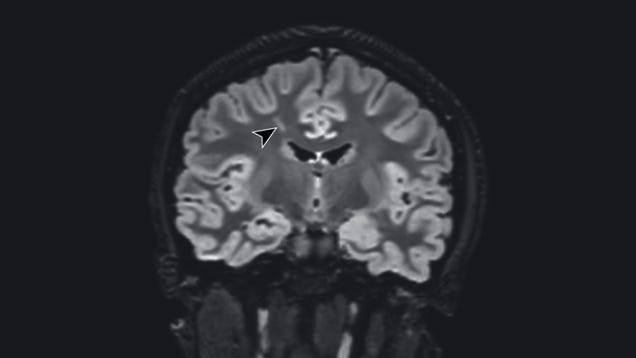

Researchers in California suspect that covid-19 triggered sudden mental illness in at least two of their teenage patients. Though they caution that a causative link remains uncertain, they say they’ve found evidence of antibodies attacking the brain of their patients post-infection, which could help explain the…

Source: Gizmodo – Doctors Say Mild Covid-19 Likely Triggered Psychiatric Illness in Two Teen Patients